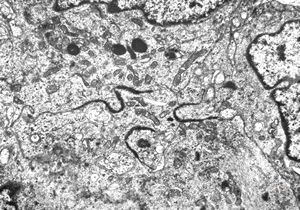

rabbit spinal cord trauma